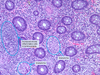

What is seen here?

Pseudomembranous colitis

- “Volcano eruption” of neutrophils and dead cells is common

- Increased chronic inflammatory cells in lamina propria